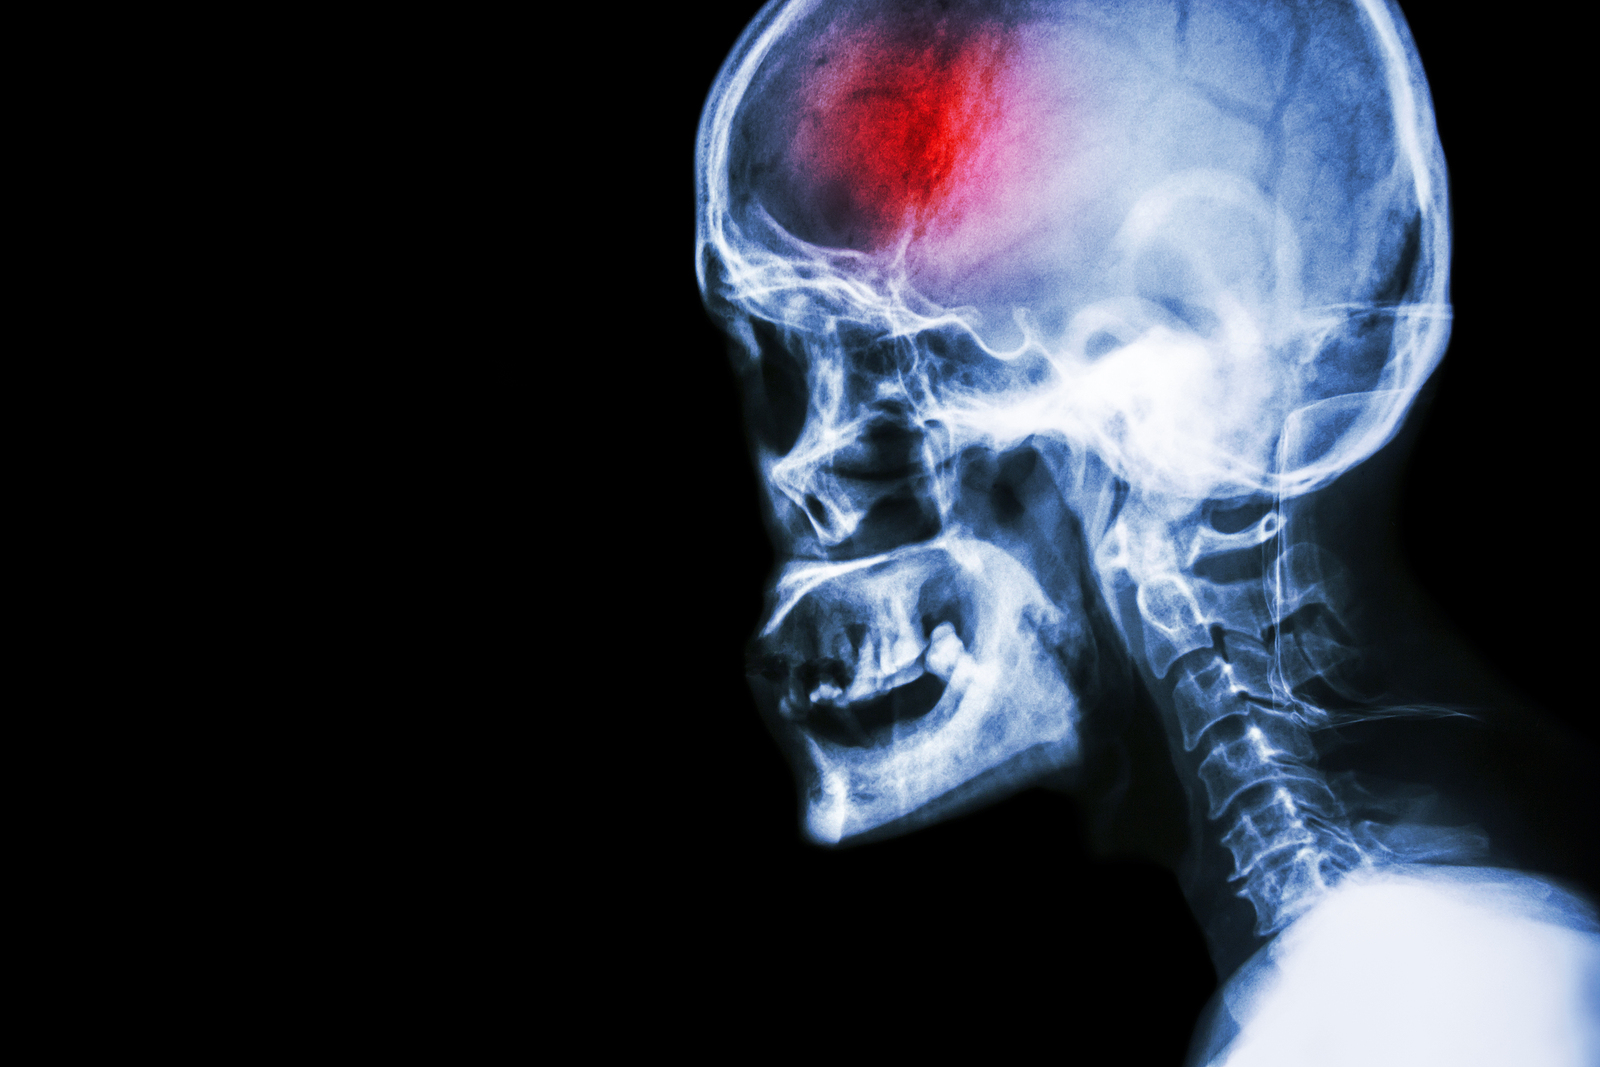

What is a stroke?

A stroke (previously known as a cerebrovascular accident) when there is a decreased flow of blood to the brain from either a blockage in the blood vessels that supply the brain (ischemic stroke), or a bleed from the blood vessels that supply the brain (hemorrhagic stroke). When the blood flow to the brain is blocked it prevents the brain from getting the needed oxygen and nutrients to function. Without oxygen the brain cells can be permanently damaged or die and the physical and mental functions related to that area of the brain will be affected. A stroke is a medical emergency and rapid treatment is crucial to decreasing the damage caused by a stroke.

Types of strokes

There are three types of strokes:

- Ischemic stroke: a stroke that is caused by a blockage (clot) that disturbs the blood flow to the brain.

- Hemorrhagic stroke: a stroke that is caused by a bleed that disturbs the blood flow to the brain and puts pressure on the surrounding tissue.

- Transient ischemic attack: often referred to as a “mini-stroke” or TIA, where the blood flow to the brain is temporarily disturbed and as a result causes temporary signs and symptoms of a stroke that resolve quickly .